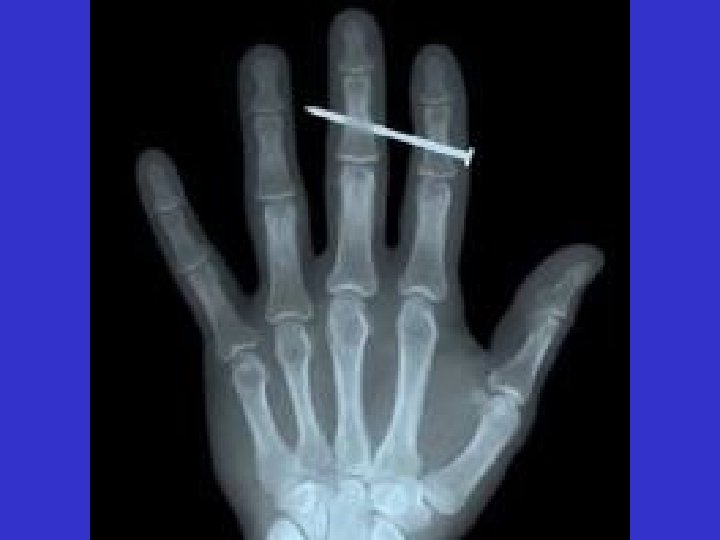

Pneumatic Tools Powered by compressed air Includes nailers, staplers, chippers, drills & sanders Main hazard - getting hit by a tool attachment or by a fastener the worker is using with the tool Take the same precautions with an air hose that you take with electric cords Nail Gun Cut-Away View

Fatal Fact Employee killed when struck in head by a nail fired from a powder actuated tool. Tool operator was attempting to anchor a plywood form in preparation for pouring a concrete wall

Easily Penetrated Material Avoid driving into materials easily penetrated unless materials are backed by a substance that will prevent the pin or fastener from passing through Also, don’t drive fasteners into very hard or brittle material that might chip or splatter, or make the fasteners ricochet